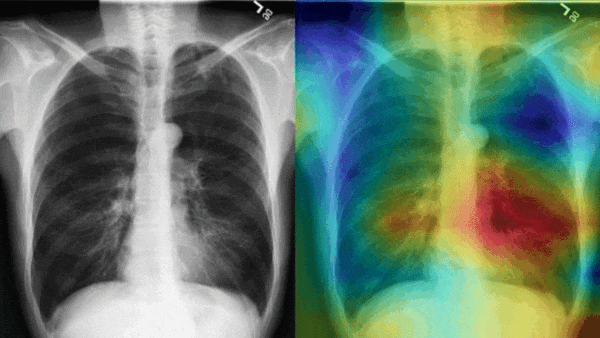

X-rays and charts about AI use in radiology

Radiologists Eye AI: Radiologists increasingly rely upon computer vision.

AI lately has achieved dazzling success interpreting X-rays and other medical imagery in the lab. Now it’s catching on in the clinic. Roughly one-third of U.S. radiologists use AI in some form in their work.